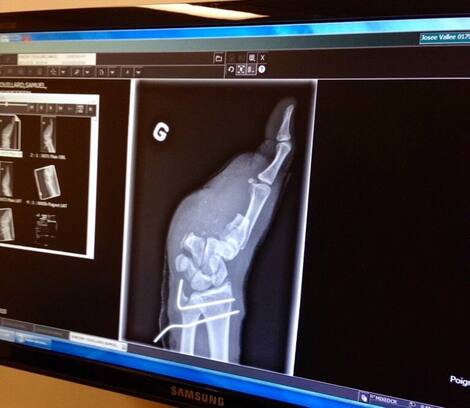

In September 2015, his life changed. The young man, who was a passenger plane pilot at the time, was hit by the moving propeller of the Cessna plane. He lost four fingers on his left hand.

On the day of his accident, a doctor arranged to keep muscles and ligaments in his arm so he could receive an electric arm. Many experts have judged that i-digit motorized fingers are the only prosthesis that can meet their needs.